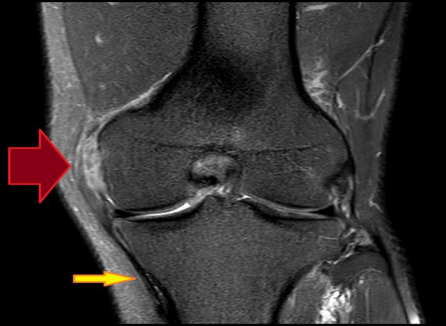

For acute knee injuries, an MRI is extremely helpful. An MRI can provide information about severity (complete vs. partial rupture) and location (avulsion vs. mid-substance tear). Of course, an MRI will also pick up associated injuries. For chronic conditions, it may be helpful to employ an MRI if and only if the anticipated results of the test will dictate management (Figure 4).

Figure 4: An MRI showing a high grade MCL tear proximally (red arrow). The yellow arrow points to intact ligament distally.